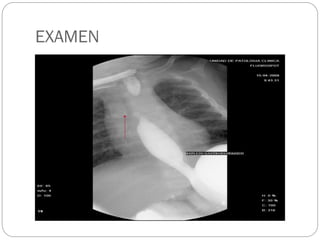

 EXAMEN

ENSOFAGOGASTRODUODENOSCOPIA

 ESTE EXAMEN ES UTILIZADO PARA EL

REFLUJO GASTROENSOFAGICO.

EXAMEN

 REFLUJO

DIAGNOSTICO  RGE CLINCOYDEPENDE DE LOS SINTOMAS.  EXAMEN ENSOFAGOGASTRODUODENOSCOPIA  ESTE EXAMEN ES UTILIZADO PARA EL REFLUJO GASTROENSOFAGICO.